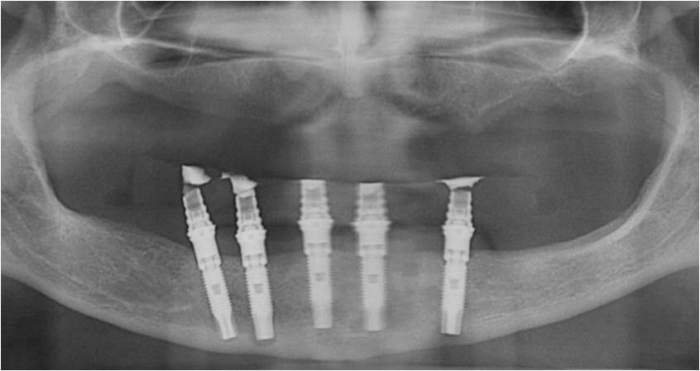

Raio X das próteses sobre implantes superiores e inferiores